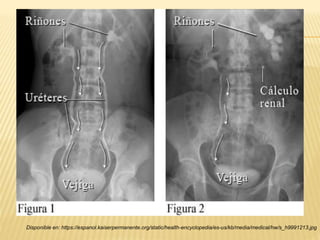

“PIELOGRAFÍA INTRAVENOSA”

Disponible en: https://espanol.kaiserpermanente.org/static/health-encyclopedia/es-us/kb/media/medical/hw/s_h9991213.jpg

“RADIOGRAFÍA Y ECOGRAFÍA DIRIGIDA”

 80-90% de los cálculos

son visibles.

 Imágenes radiopacas.

Se valora:

- Forma (circulares,

ovoides, amorfos).

- Tamaño (1-8 cm de

diámetro).

- Número